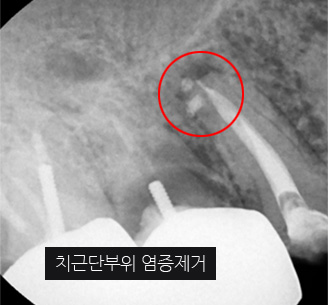

신경관이 막혀 있는 경우 재 신경치료로 낫지 않는 경우, 포스트가 있어 재 신경 치료를 할 수 없는 경우, 치아 뿌리까지 염증이 심하지만 이러한 염증을

제거 할 수 없는 경우, 고운미소 치과에서는 치조골 주위 염증조직을 제거하는 치근단절제술을 시행합니다.

기존 신경치료는 양호한 상태이나 치근부위에 염증과 치조골 소실이 진행 중

치아 뿌리 쪽 잇몸을 절개하고 치조골 부위의 염증조직을 제거. (난이도 중)